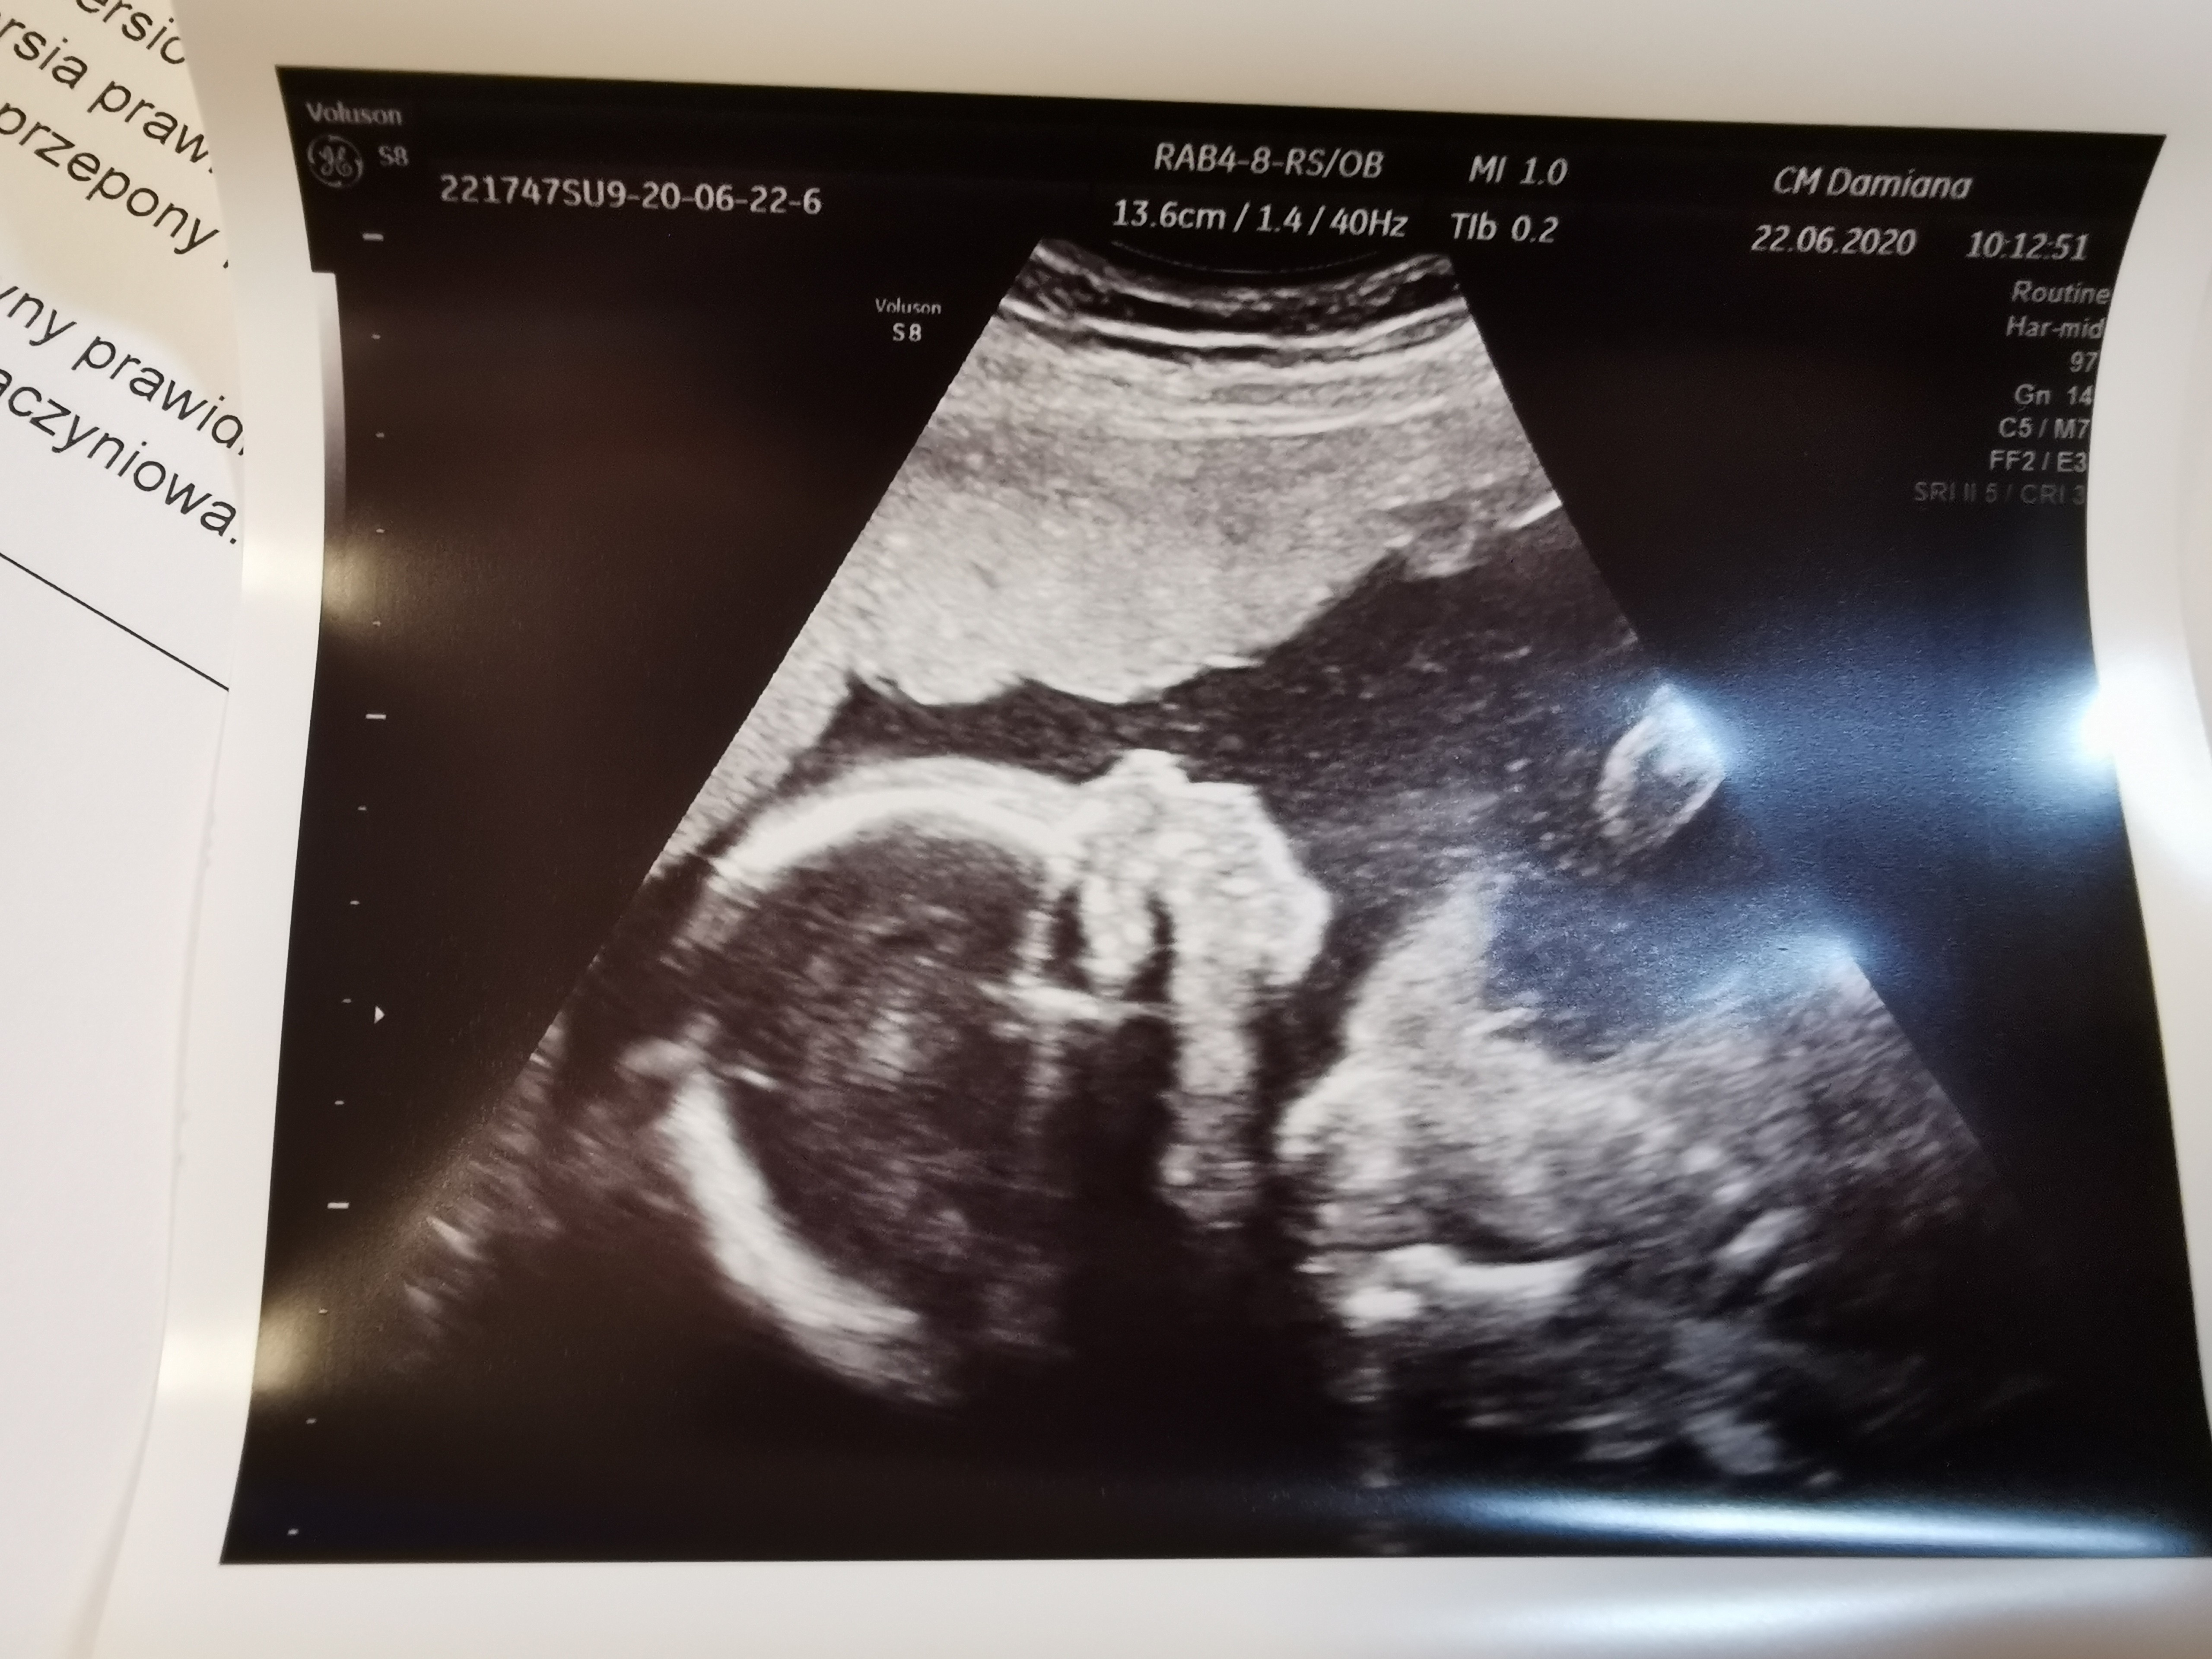

Wszystko widać pieknie było, żadnego chowania się, 450g maleństwa

Wszystko na swoim miejscu, pysiak słodki

No i dzisiaj to tak "tu główka, a tu w przekroju, polozenie miednicowe, tu kość udowa, a tu nerki, a tu pecherz, a tu rączki, a widzi pani łokieć, a tu dłon i paluszki itd."

Wszystko prawidłowo, zapowiada się duży zawodnik, stopy też konkret